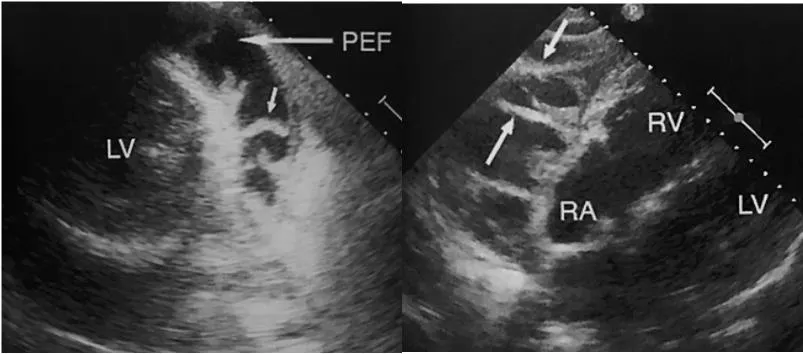

A2. RA systolic collapse (early finding)

PSLX, AP4C view에서 관찰

Early sign (높은 민감도와 특이도)

: RA가 RV보다 pressure 낮게 때문에, pericardial sac에 있는 fluid로 부터의 compression에 더 영향을 많이 받기 때문

A3. RV diastolic collapse (most specific)

Most specific 한 sign (75~90%) 민감도는 48~60%

Long axis에서 RV free wall이 diastolic collapse 있는지 . 특히 early diastolic때